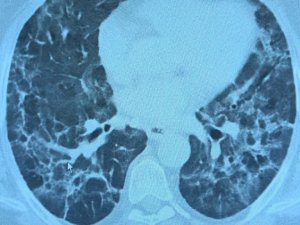

Korona virüs geçiren hastalarda yeni klinik bulgular: "Uzamış Covid ve post Covid"